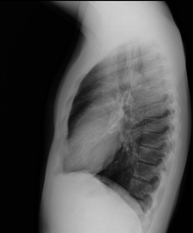

- Tòrax

- RX Tòrax

Tècnica que usa els raigs X a través de la qual s'obtenen imatges de la caixa toràcica (cor, pulmó, arcs costal, clavícules, etc.) per al seu estudi. - RX Ester